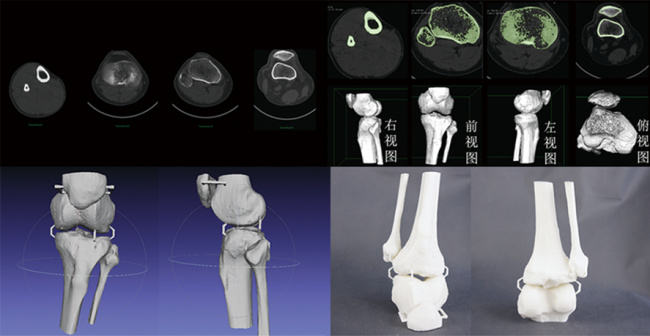

杭州博型科技在膝关节股腓髌胫骨手术

3D建模, 3D打印技术, 3D打印骨骼By 杭州博型3D打印2023年4月28日

在本文中,我们将重点关注杭州博型科技在膝关节股腓髌胫骨手术方面的3D打印和CT数据三维建模技术应用。 一、背景…